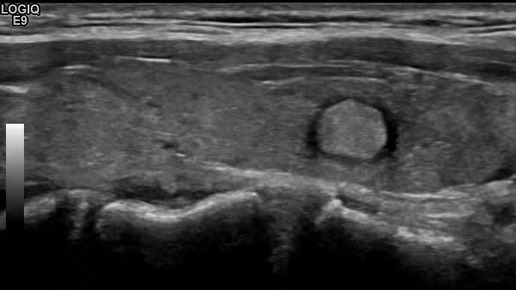

Видео к статье "Стратификация узлов щитовидной железы. TI-RADS-3" https://dzen.ru/a/Zv4svErHVi-eImKZ

Ультразвуковые находки от врача УЗД Зорина Я.П.